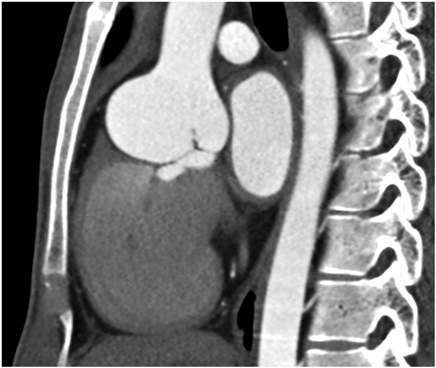

胸部造影CT検査

バルサルバ洞径47.9 mm,上行大動脈19.7 mm(Fig. 1).

Fig. 1 胸部造影CT検査

右バルサルバ洞が前方に拡大し,バルサルバ洞の最大径は47.9 mmであった.